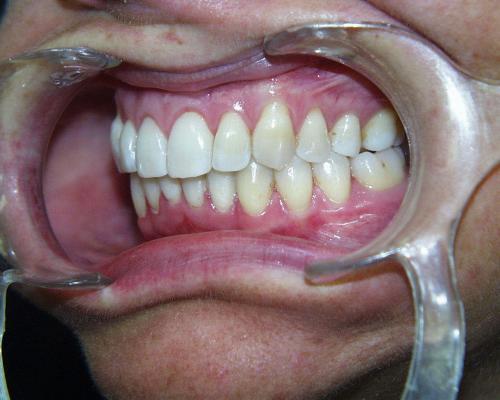

Vor der Behandlung

Fallbeispiel 4 zeigt einen häufigen Befund bei erwachsenen Patienten: Die Stellung der Schneidezähne hat sich in beiden Zahnbögen im Laufe der Jahre erkennbar verschlechtert, und die Patienten fühlen sich dadurch zunehmend beeinträchtigt. Die in diesem Beispiel nur geringgradigen Abweichungen im Oberkiefer ließen sich mit nahezu unsichtbaren, herausnehmbaren Alignerschienen behandeln, während die Korrektur der stärkeren Schachtelstellung der unteren Frontzähne eine festsitzende Zahnspange erforderte. Auch hier ist nach der Korrektur die Verwendung innenliegender aufgeklebter Stabilisierungsdrähte über viele Jahre hinweg ratsam.